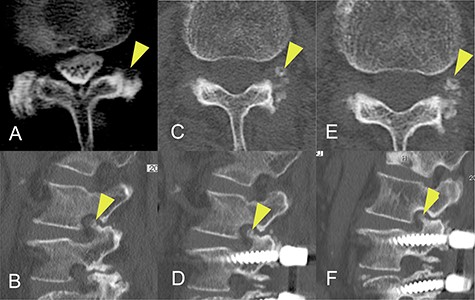

The patient was an 82-year-old Japanese woman who had presented 2 months earlier with pain and numbness in her left lower extremity. She had a history of vertebral fracture at L1 4 months previously for which she had been treated with a lumbar orthosis for 2 months (Fig. 1). Magnetic resonance imaging of the lumbar spine demonstrated foraminal stenosis at the L2–L3 level (Fig. 2A). CT images of the lumbar spine revealed ossification in the capsular portion of the ligamentum flavum around the L2–L3 facet joint (Fig. 2B–D). She underwent L2–L3 foraminotomy with excision of the capsular portion of the OLF. The patient’s symptoms disappeared immediately after surgery. Postoperative CT scans showed good decompression at the operated level (Fig. 2E and F).

Magnetic resonance and computed tomography (CT) images acquired at the time of onset of radiculopathy. (A) Sagittal T1-weighted magnetic resonance image showing moderate foraminal stenosis at the L2–L3 level. (B) Sagittal CT image showing ossification of the ligamentum flavum protruding into the foramen. (C, D) Axial CT image showing OLF in the capsular portion. (E, F) Postoperative CT image confirming adequate removal of the ossification of the ligamentum flavum.